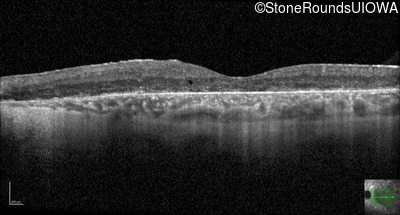

Optical Coherence Tomography - Left - 20/40 -1

Exemplar / OCT Stack

OCT Stack